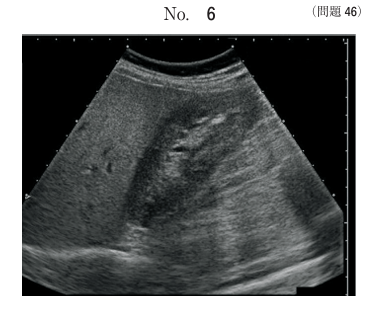

午前/問題46

上腹部超音波検査において、考えられる病変はどれか。

1.水腎症

2.腎結石

3.脂肪肝

4.閉塞性黄疸

5.肝内胆管結石